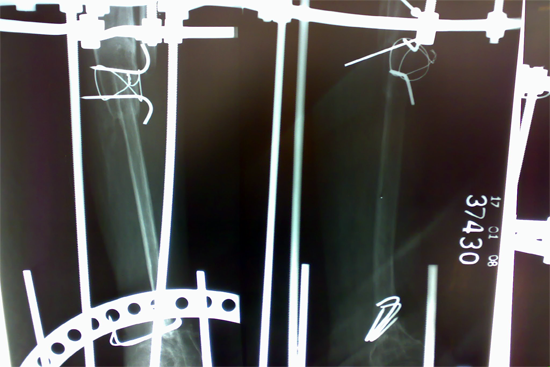

Tibialisation of Fibula

Method

We have done Huntington technique by stage ilizarov procedure. Here is the diagrammatic representation of our method.